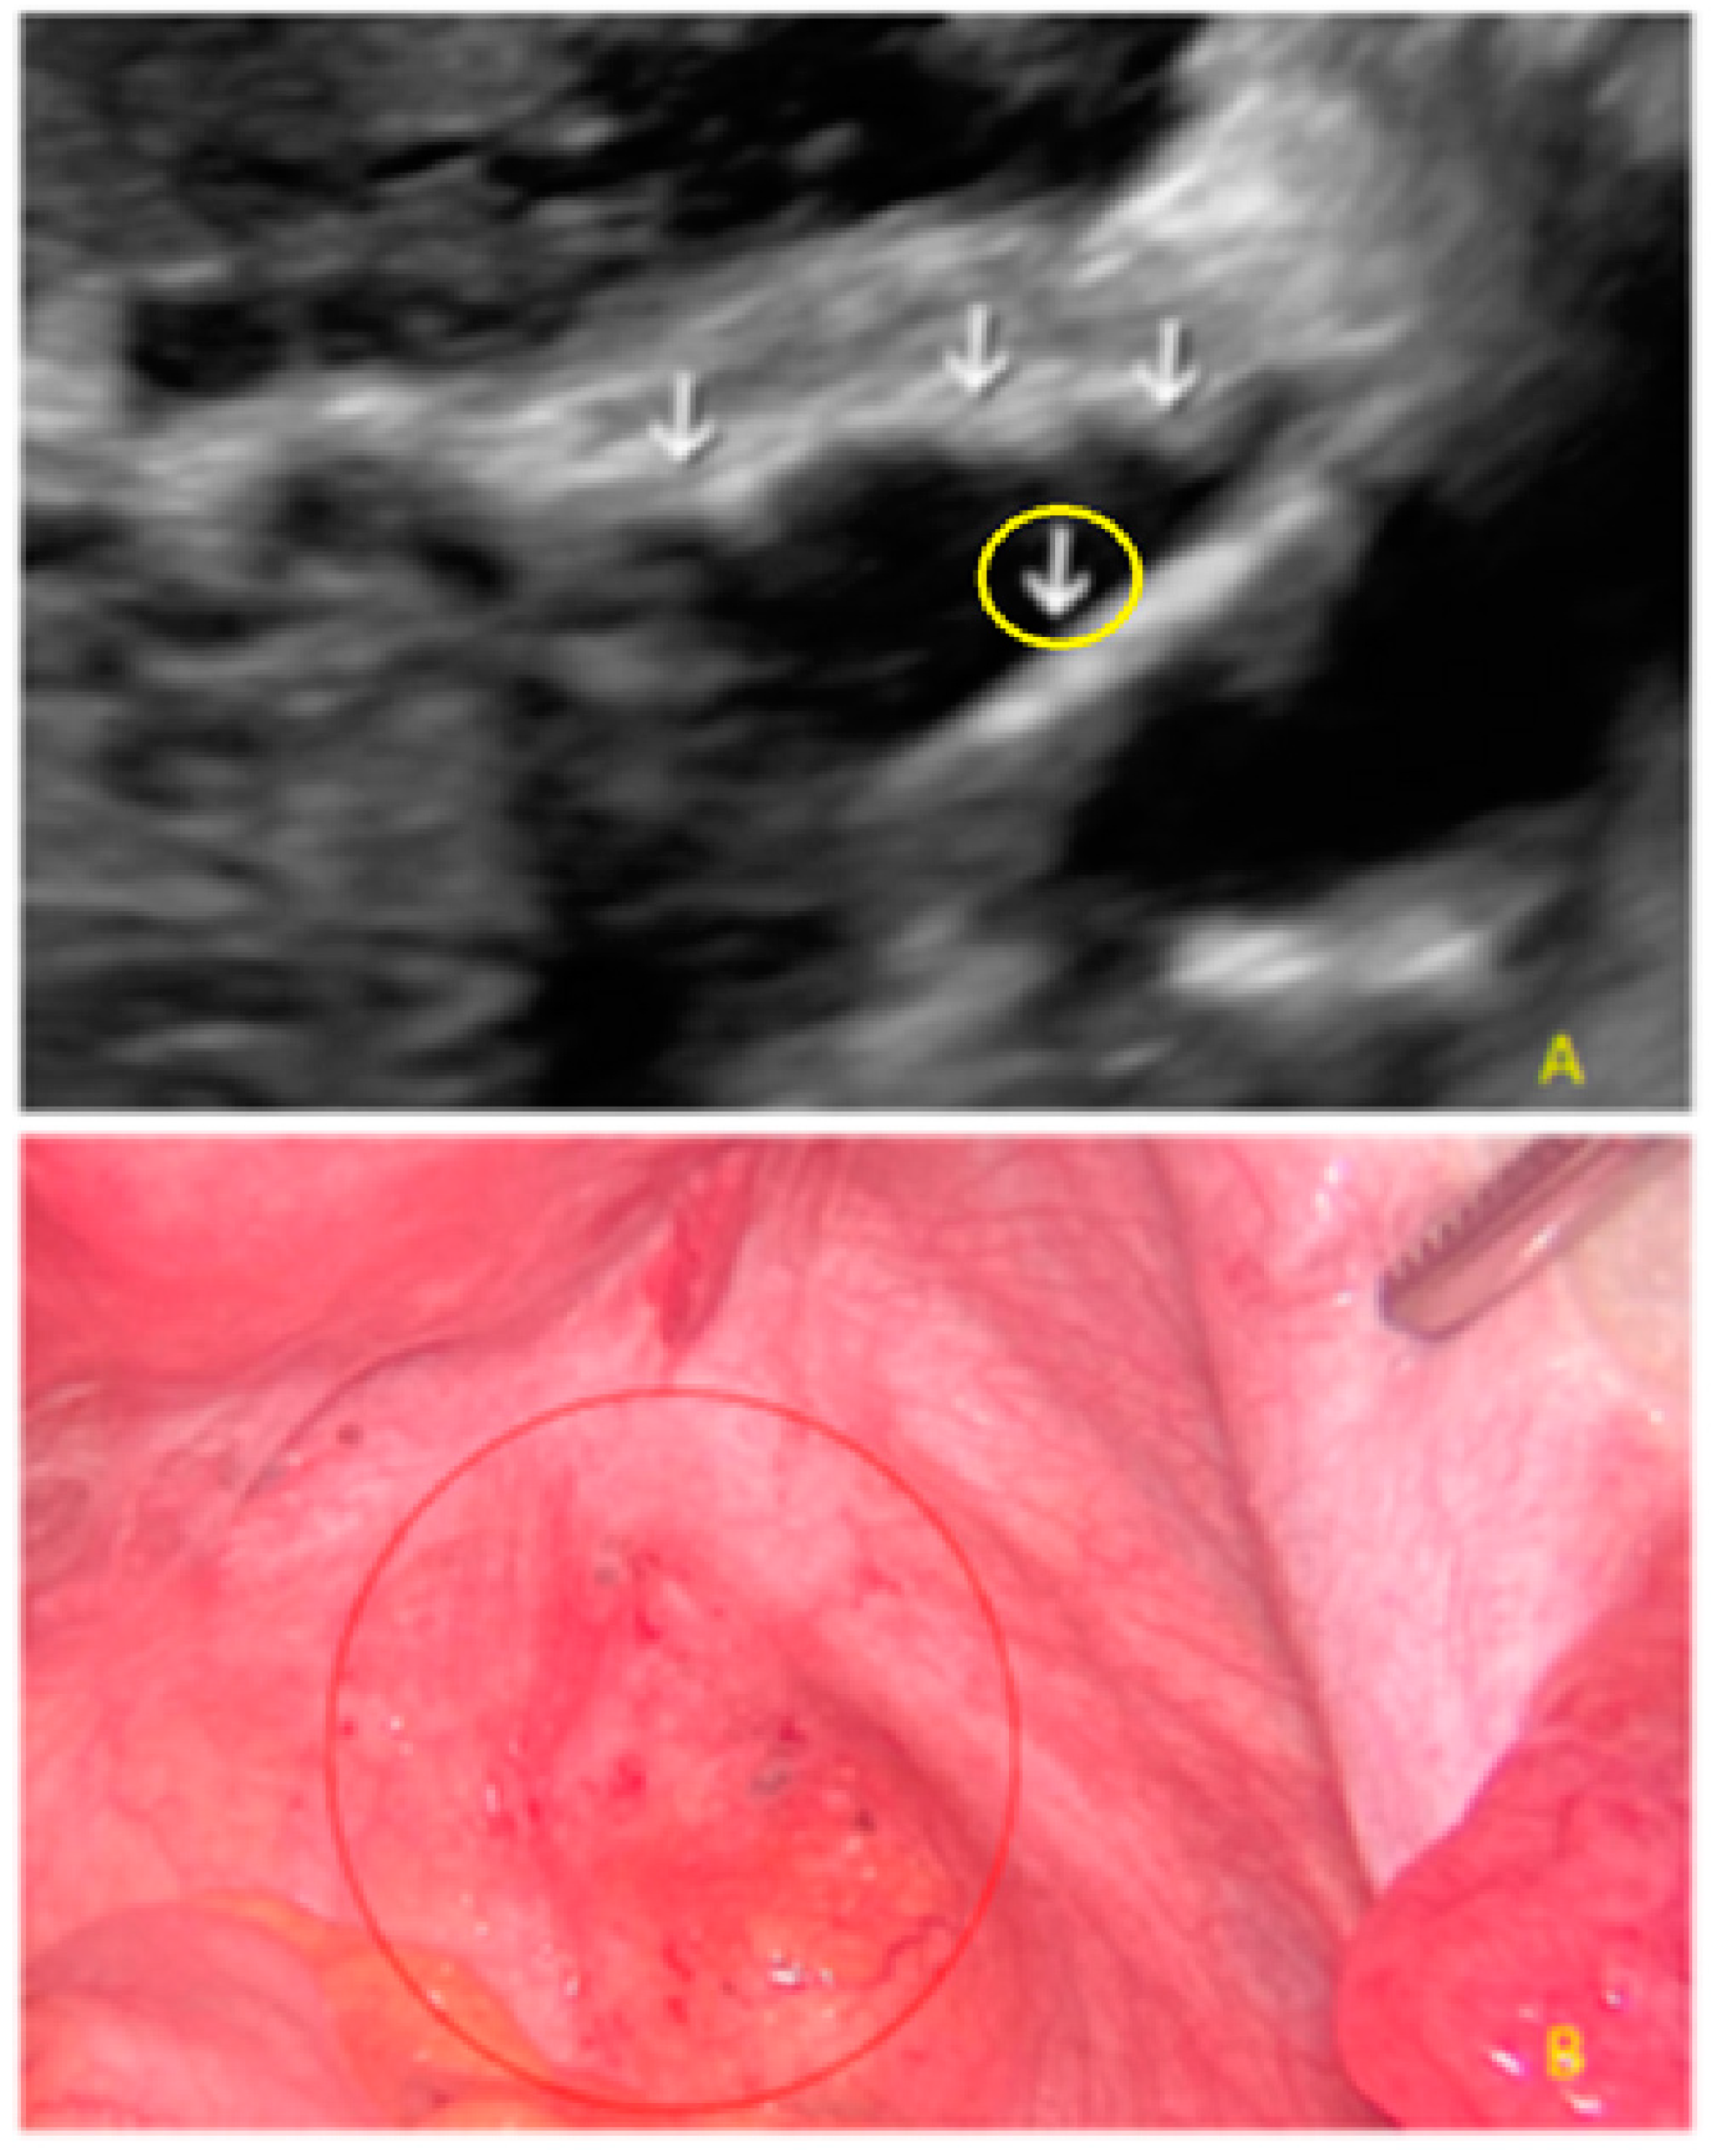

- The presence of hypoechogenic associated tissue (hypoechoic areas surrounding a small cyst area; we called this a “hat”). This tissue does not protrude or invaginate the peritoneal surface.

- The lesion may be convex, protruding from the peritoneal surface into the peritoneal cavity (we called this “bulging”), or it may appear as a concave defect in the peritoneum (we called this a “pocket”).